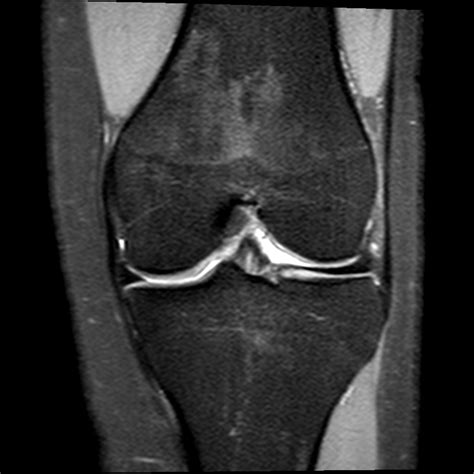

Dealing with knee pain can be incredibly disruptive, affecting everything from your daily commute to your ability to enjoy physical activities. When persistent discomfort, swelling, or instability occurs, medical professionals often turn to advanced diagnostic tools to pinpoint the underlying issue. An MRI of knee (Magnetic Resonance Imaging) is considered the gold standard for visualizing the complex internal structures of the knee joint. Unlike X-rays, which primarily show bones, an MRI provides a high-resolution, detailed view of soft tissues, including ligaments, tendons, cartilage, and muscles, allowing doctors to make accurate diagnoses without invasive procedures.

Your doctor might recommend an MRI of knee when a physical examination and other imaging tests, such as X-rays, do not provide enough information to explain your symptoms. Because the knee is a complex hinge joint subjected to significant stress, it is susceptible to various types of injuries and degenerative conditions. An MRI is exceptionally effective at detecting subtle abnormalities that might otherwise go unnoticed.